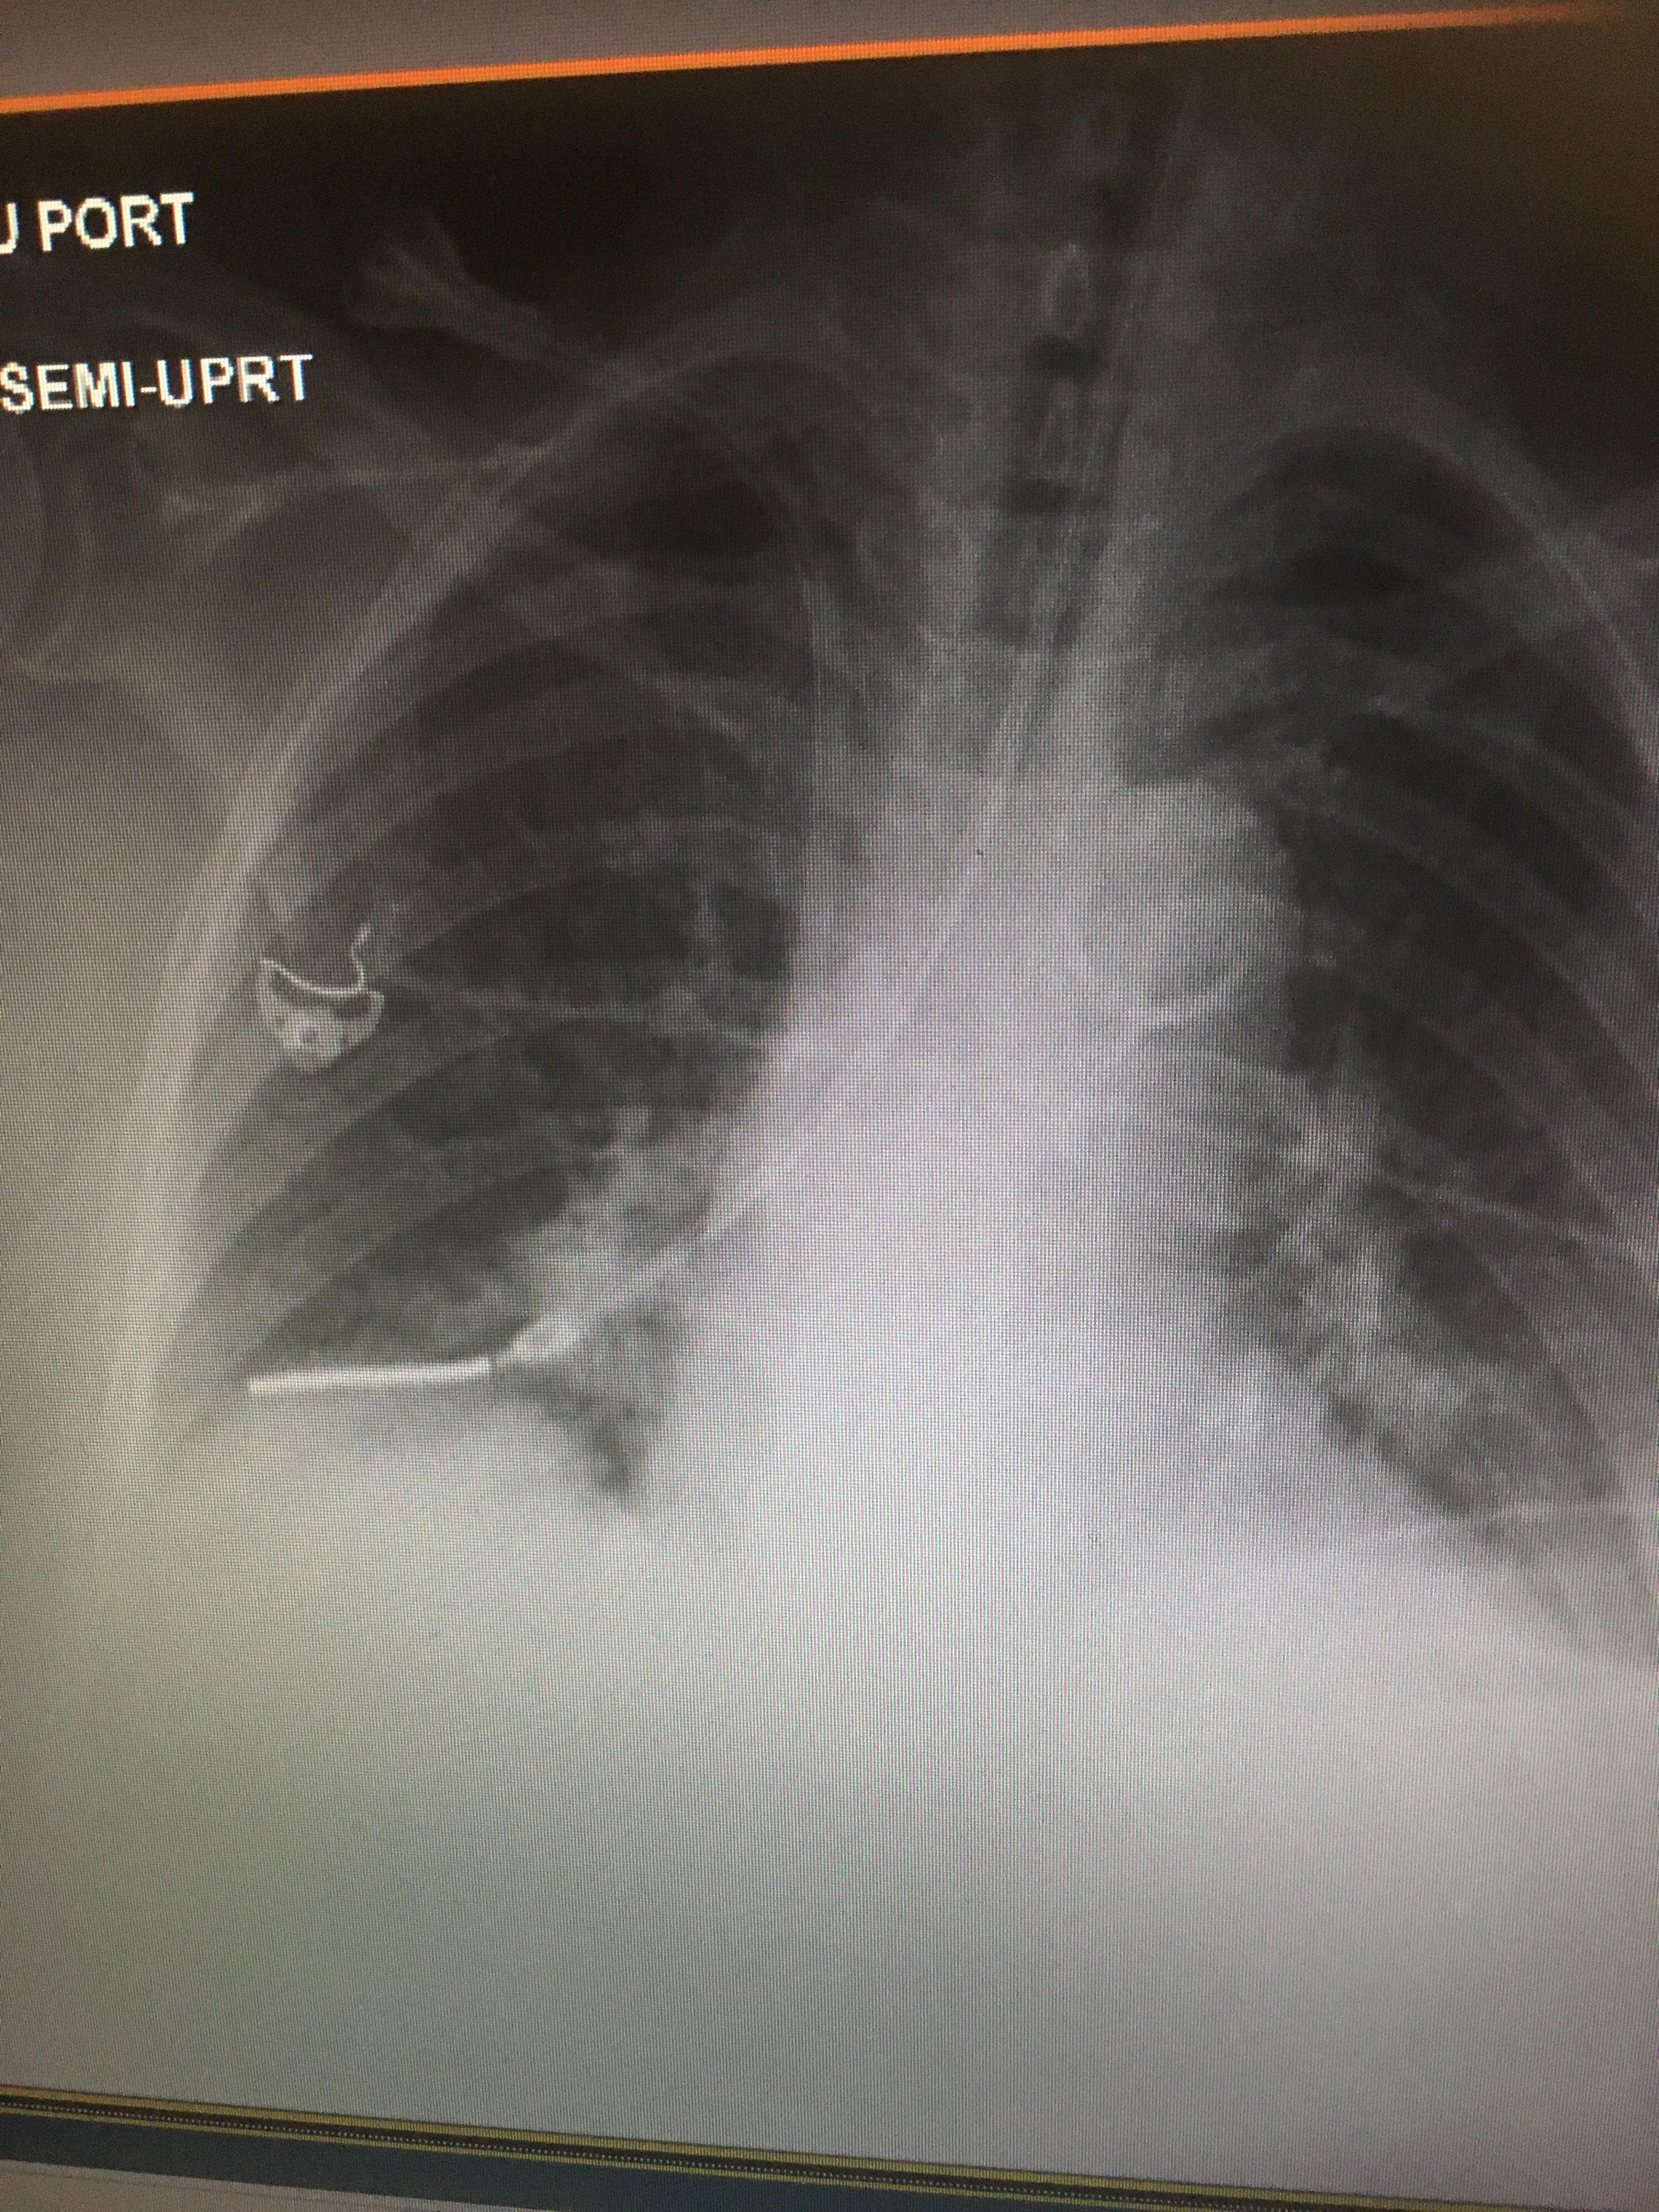

Xray confirmation of my duotube placement r/nursing Breastfeeding And Xray In summary, the acr recommends considering screening imaging in pregnant and lactating women under the age of 30 who are at high risk. In this article, we describe the physiologic changes of the breast induced by pregnancy and lactation; Where possible x rays are avoided during pregnancy but there is no reason to avoid them during breastfeeding. We can say. Breastfeeding And Xray.

Chest radiographs in pregnancy The BMJ Breastfeeding And Xray Discuss the safety and utility of ultrasound, mammography, and. Where possible x rays are avoided during pregnancy but there is no reason to avoid them during breastfeeding. In this article, we describe the physiologic changes of the breast induced by pregnancy and lactation; In summary, the acr recommends considering screening imaging in pregnant and lactating women under the age of. Breastfeeding And Xray.